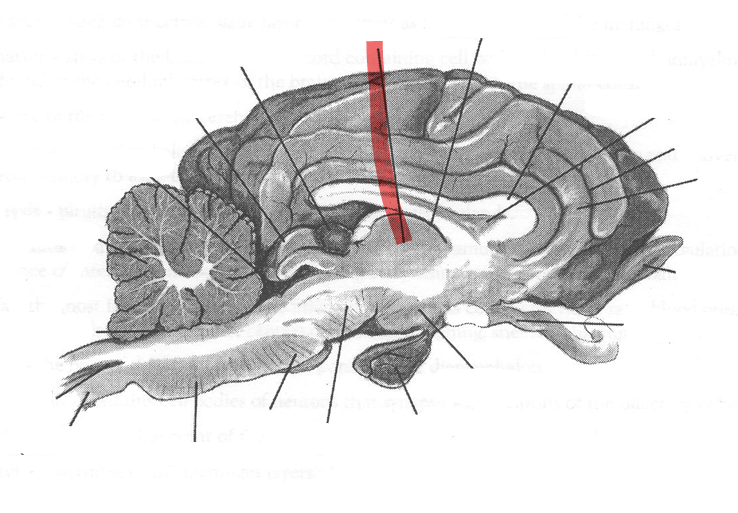

Identify highlighted arrow

Pons